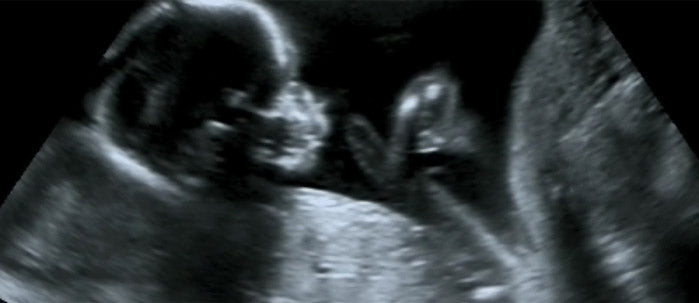

In every pregnancy, there is a risk of health problems for mother and child. If your doctor tells you that you have a high-risk pregnancy, it means that there is a higher chance of you and/or your baby developing health problems. However, this also means that you will get extra attention during your pregnancy to make sure things go smoothly.